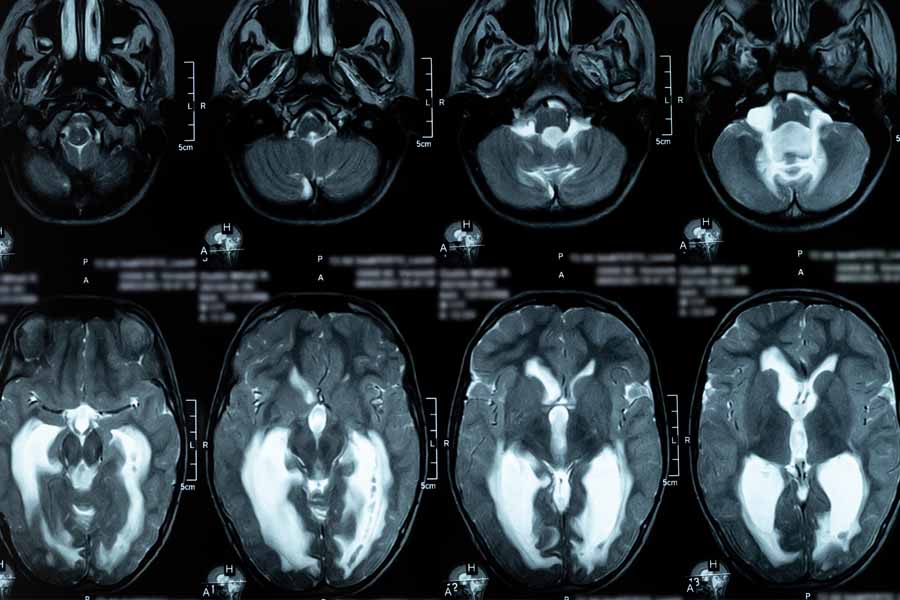

Hydrocephalus happens when too much cerebrospinal fluid (CSF) builds up in the brain. This can increase pressure and affect how the brain works. It may be present at birth or develop later in life from injury, infection, bleeding, or a blockage in the CSF pathways.

MRI, CT, and CSF flow studies help identify blockages, pressure changes, or Chiari-related problems. These tests guide decisions about surgery or shunt placement.

Chiari malformation happens when part of the lower brain sits too low and pushes into the spinal canal. This can block the flow of cerebrospinal fluid (CSF) and cause headaches, neck pain, and neurological symptoms. Some people are born with it and do not notice symptoms until later in life.

Syringomyelia is a condition where a fluid-filled cavity (called a syrinx) forms inside the spinal cord. It often develops from Chiari malformation but can also follow injury, infection, or spinal surgery. As the syrinx grows, it can damage nerves and affect movement and feeling.